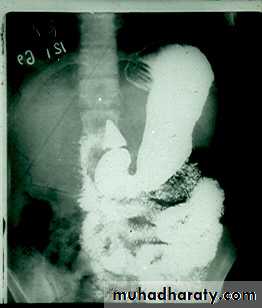

Barium meal Fluoroscopy + spot films Preparation

The Normal Anatomy of Stomach1- Shape.2-Size.3-Site.4-Anatomical parts.5-Mucosal pattern.

Normal Anatomy of DuodenumDuodenal cap.Duodenal loop